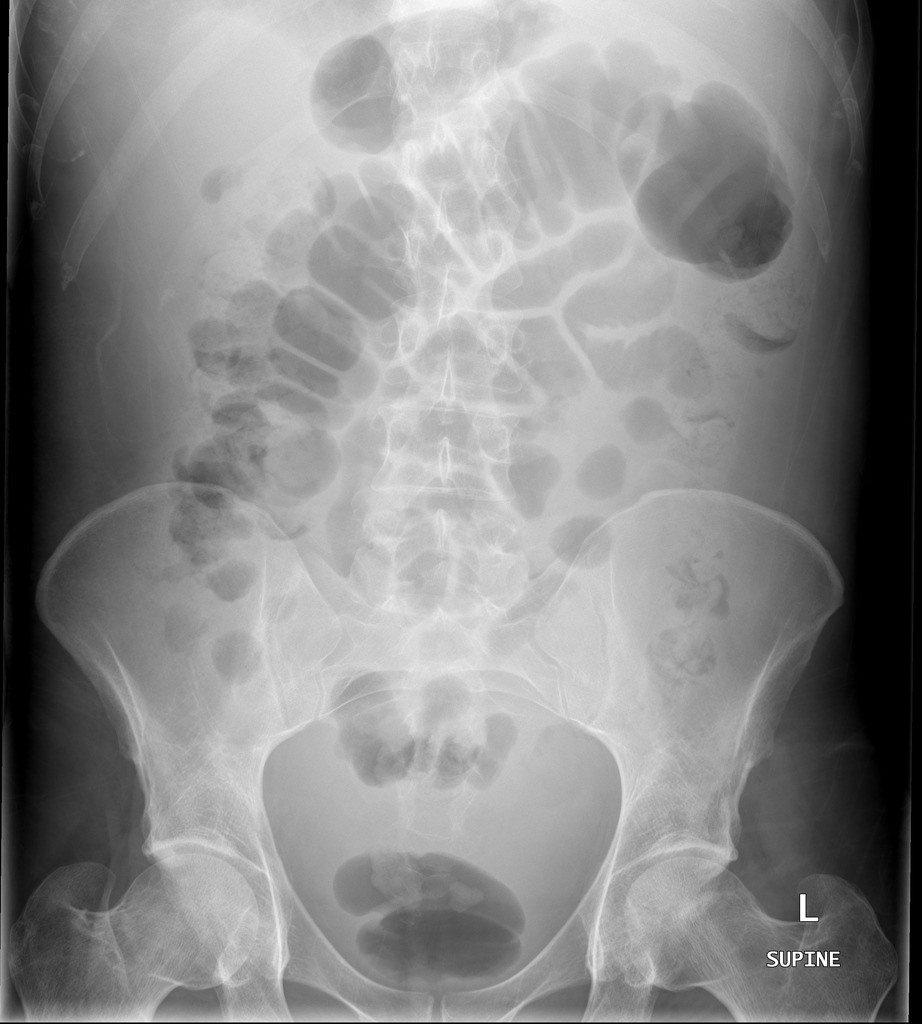

کیس اول تشخیص آسیت در رادیوگرافی :

آقایی 35 ساله با درد شدید شکمی و شکم حاد

در رادیوگرافی ساده شکمی روبرو مایع جمع شده به راحتی بین لوپ های روده مشخص است که نشان دهنده آسیت می باشد .میدونید کجا رو میگم؟ قسمت مرکزی شکم رو ببینید !

لوپ های لوسنت روده که بین شون رگه های رادیواپاک تر و سفیدتر دیده میشه!

در این گرافی شما لوپ های روده که تراکم بیشتری در قسمت مرکزی دارند رو مشاهده می کنید.داخل لوپ ها لوسنت هست و دیواره نازکشون مشخصه! نکته اینه که اگه بین لوپ ها رو ببینید کنتراست بیشتری نسبت به داخل لوپ ها دارند. کنتراستی شبیه به مایع !

پس چه نتیجه ای میگیریم؟ ایول ! مایع بین لوپ ها رو پر کرده

این مایع میتونه هر چیزی باشه که اسمشو میذاریم آسیت! این یکی از روش های تشخیص بود .